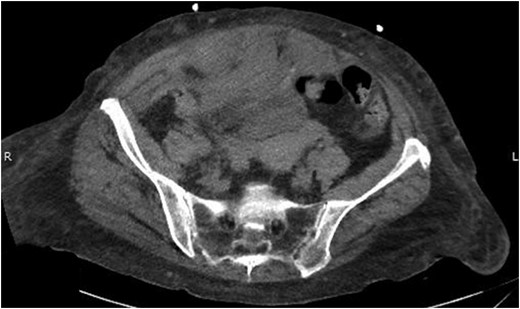

On examination she was pale, had a blood pressure of 97/52 mm Hg and heart rate of 74. On abdominal examination, she was distended and tender in all four quadrants. Her hemoglobin (Hb) was 4.7 g/dl, white blood cell count was 11.4 × 109/l and platelet count was 146 × 103/mcl. Her international normalized ratio (INR) was 1.5, which was reversed effectively with two units of fresh frozen plasma. She was transfused five units of packed cells improving her hemoglobin from 4.7 to 7.8 g/dl. An emergency contrast CT scan of abdomen and pelvis was performed which showed a large right-sided RSH extending into the space of Retzius (Fig. 1).

The following day the patient’s urine output declined progressively and she subsequently developed acute renal failure. A urinary catheter was placed but significant resistance was encountered secondary to her locally distorted anatomy from the hematoma. A repeat non-contrast CT abdomen and pelvis was therefore obtained which showed further extension of the RSH into the space of Retzius with retroperitoneal extension causing hydronephrosis (Fig. 2).

Abdominal CT scan showing the RSH extending into space of Retzius and retroperitoneum.